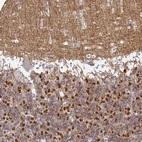

Immunohistochemistry analysis in human cerebral cortex and skeletal muscle tissues using HPA058511 antibody. Corresponding SIRPA RNA-seq data are presented for the same tissues.